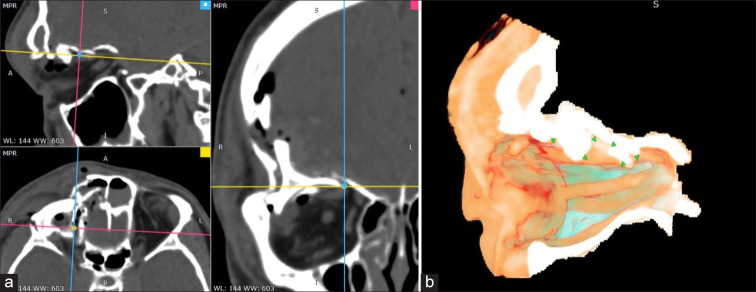

Case description: A 25-year-old male experienced a depressed orbital roof fracture resulting from a motorcycle accident. Postaccident, he reported double vision accompanied by restricted eye movement. Surgical intervention was performed to reconstruct the bone fragments compressing the ocular muscles. Postoperative day (POD) 1, the patient exhibited improved eye movement, and the double vision had resolved. POD 6 complete recovery.